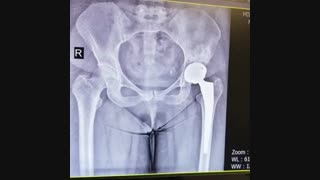

تجربه جراحی تعویض مفص لگن از زبان بیمار